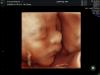

Москва. Кто был на узи у Хулаговой Л.А? Как вам врач? Хочу сходить на полноценное узи + 3д. Если есть фото 3д с ее приема, покажите, пожалуйста 🙏🏼

@maru.eg, о боже невероятно!!! Такой малыш красивый, тьфу тьфу тьфу

Значит и у меня будут такие фотографии через 2 недели🥹🥹🥹🥹🥹